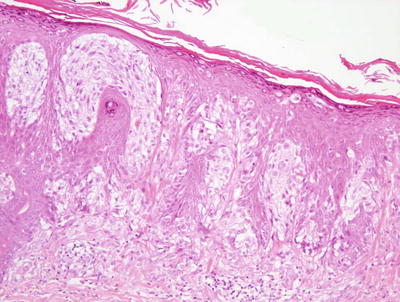

Fig. 20.5

A Becker’s nevus is characterized by a slightly acanthotic epidermis that may be papillomatous . The basal layer has increased melanin with only minimally increased number of melanocytes. Abundant large smooth muscle bundles are present in the dermis